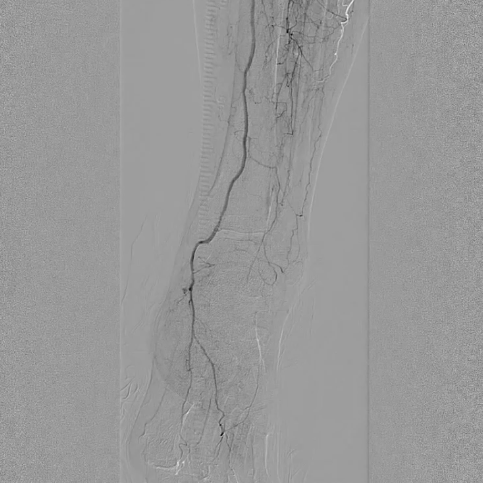

造影显示:胫腓干动脉血流恢复通畅,支架形态及位置理想,胫后动脉显影较术前明显改善;

腔内超声证实:铁支架完全张开、贴壁良好,无明显残余狭窄。